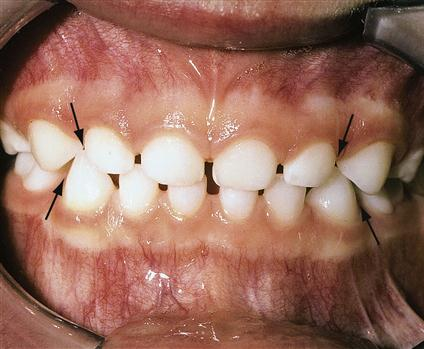

Ở giai đoạn này, thường có sự tồn tại của các khe hở tự nhiên làm thưa răng, đó là các khe hở nguyên thủy (khe hở linh trưởng), xuất hiện ngay khi răng mới mọc.

Hàm trên: nằm giữa răng cửa bên và răng nanh

Hàm dưới: nằm giữa răng nanh và răng cối sữa thứ nhất

Tuy nhiên, một số trường hợp không có các khe này.

Các khe hở nguyên thuỷ ở bộ răng sữa